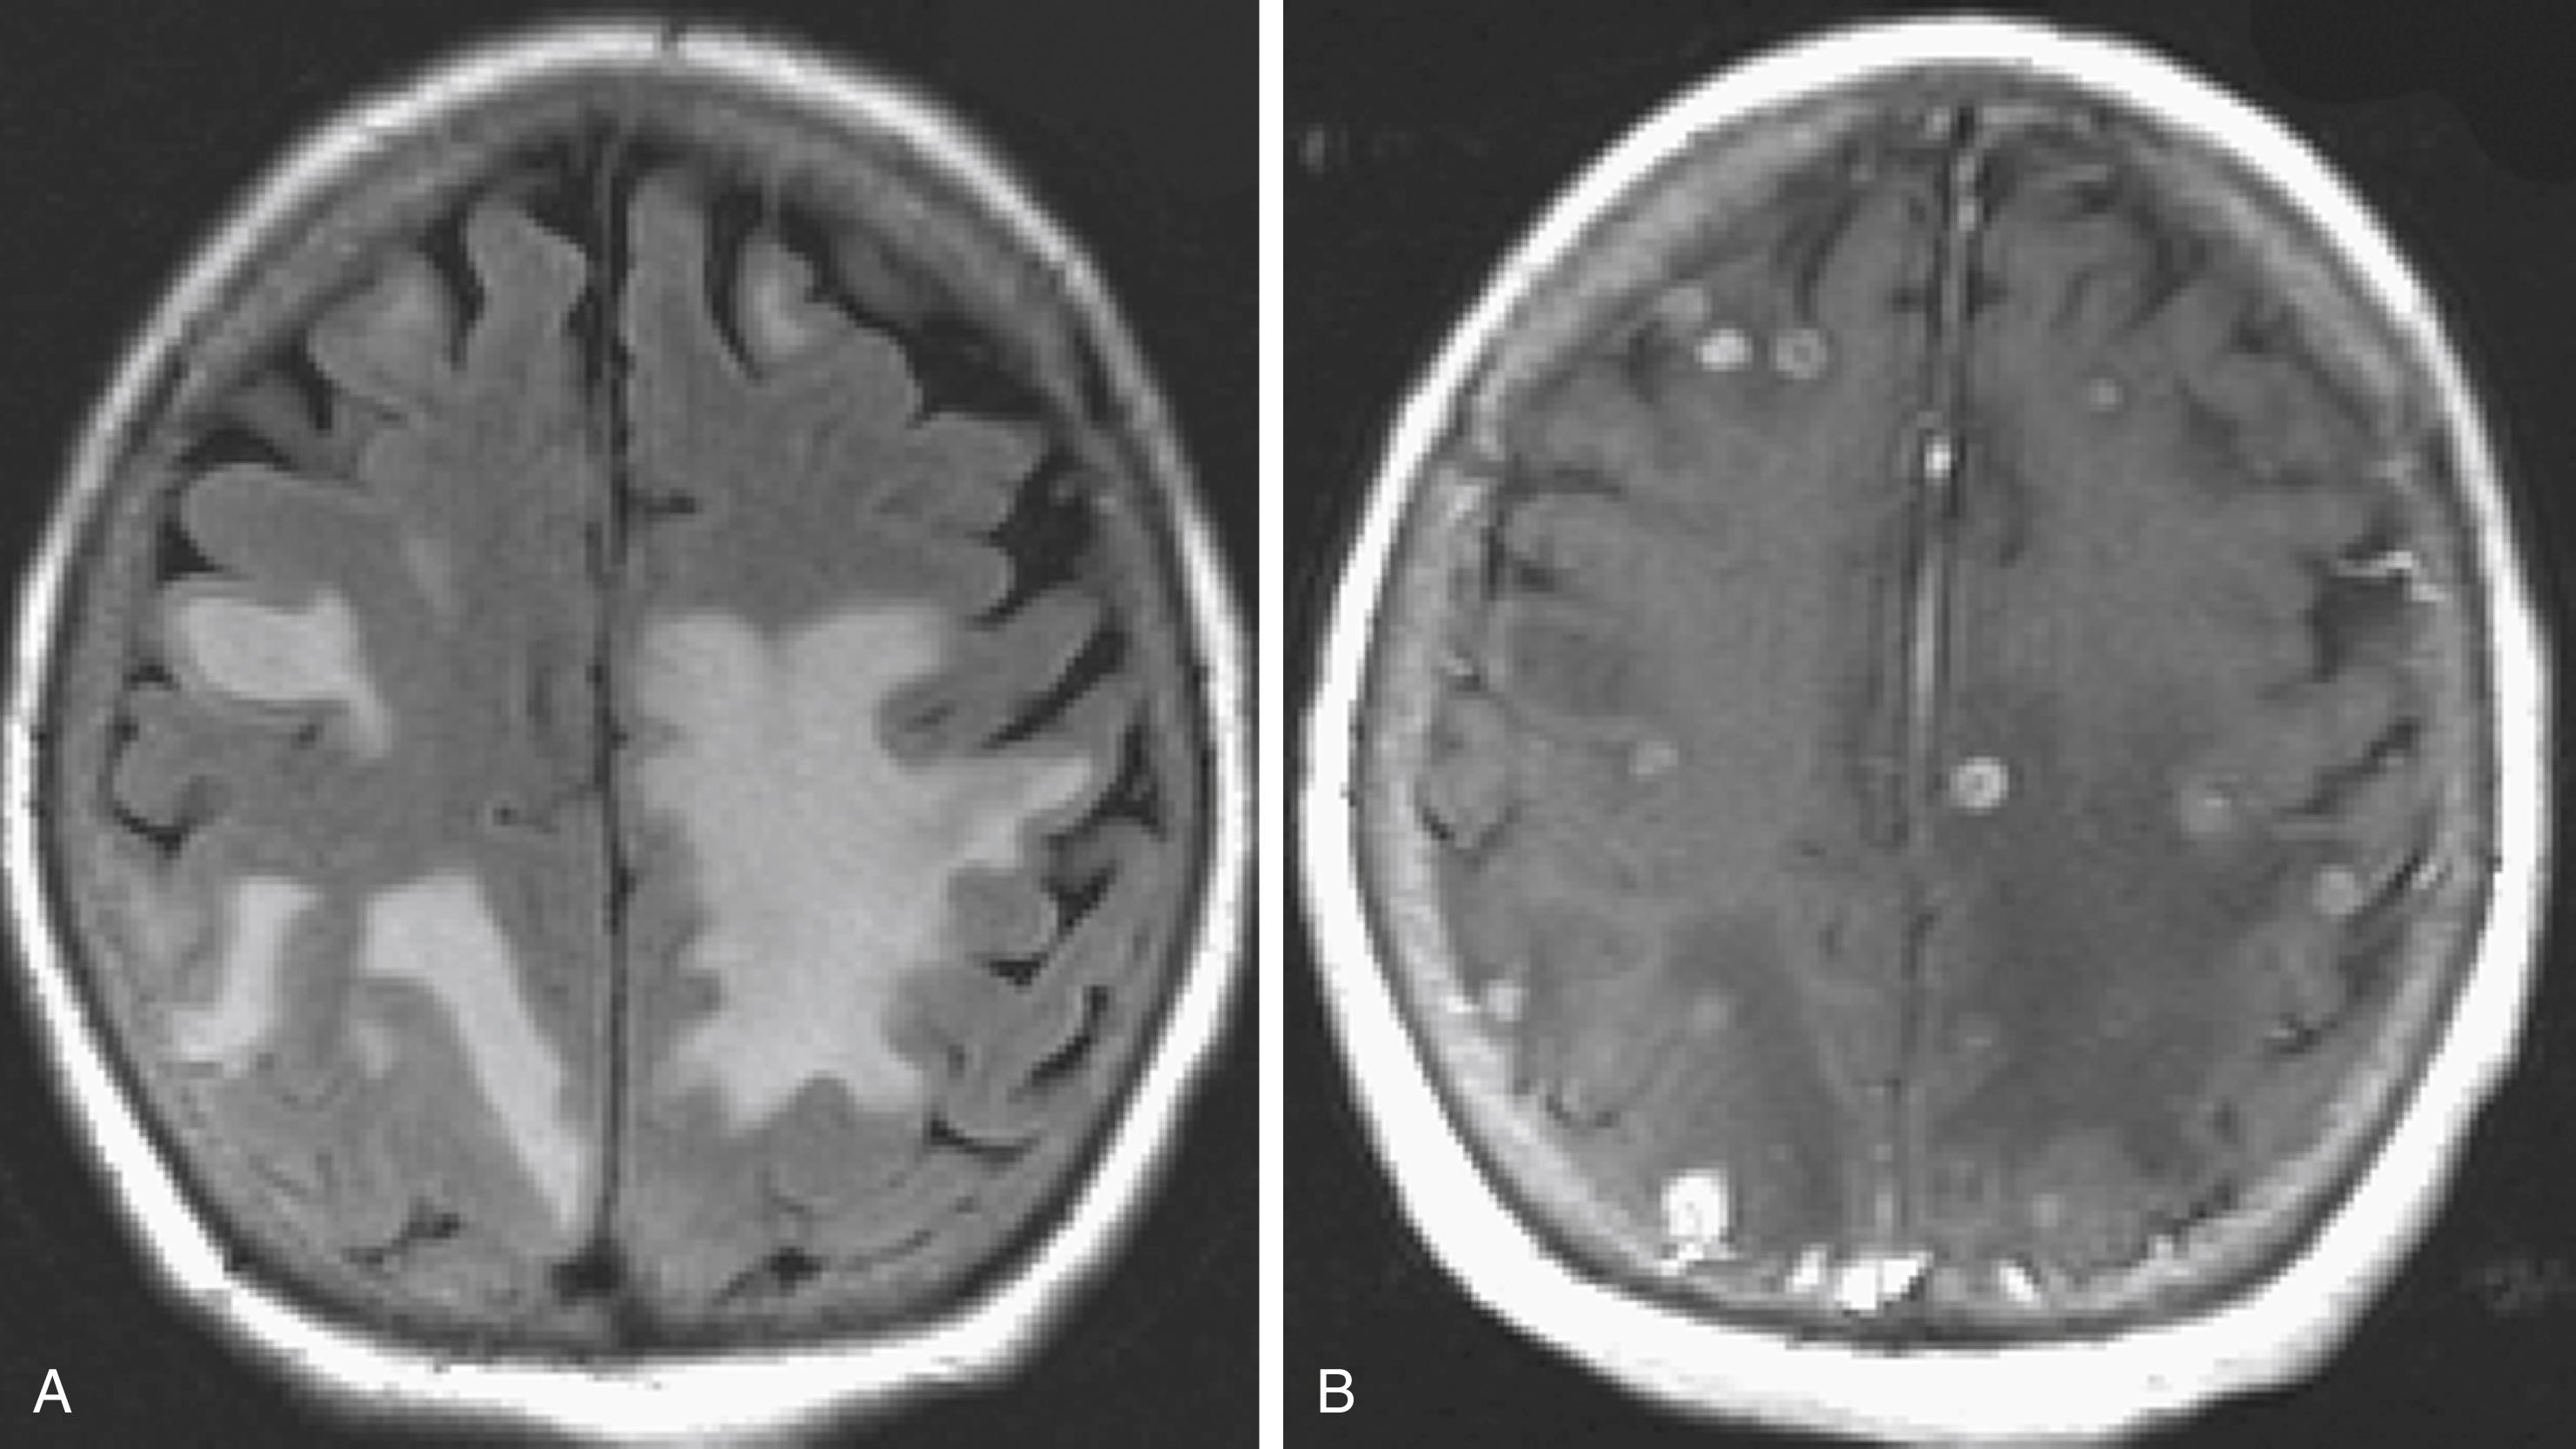

Primary CNS lymphoma (PCNSL) is a non-Hodgkin lymphoma, which in 98% of cases is a B-cell lymphoma. It once accounted for only 1%–2% of all primary brain tumors, but this percentage has been increasing, mostly because of the growing acquired immunodeficiency syndrome (AIDS) population. The peak age of onset is 60 in the immunocompetent population and age 30 in immunocompromised patients. Lesions may occur anywhere within the neuraxis, including the cerebral hemispheres, brainstem, cerebellum, and spinal cord, although the most common location (90% of cases) is supratentorial. PCNSL lesions are highly infiltrative and exhibit a predilection for sites that contact subarachnoid and ependymal surfaces as well as the deep gray nuclei.

The imaging appearance of PCNSL depends on the patient’s immune status. The tumor is hypo- to isointense on T1-weighted and hypo- to slightly hyperintense on T2-weighted images. Contrast enhancement is usually intense. In immunocompetent patients ( ) the lesion is often single and tends to abut the ventricular border ( ), and ring enhancement is uncommon ( Fig. 40.22 ). In immunocompromised patients, usually multiple, often ring-enhancing lesions are seen, which are most commonly located in the PV white matter and the gray/white junction of the lobes of the hemispheres, but the deep central gray matter structures and the posterior fossa may be involved as well. Overall, the imaging appearance appears more malignant in the immunocompromised cases and may be difficult to differentiate from toxoplasmosis. Other components of the differential diagnosis in patients with multiple PCNSL lesions include demyelination, abscesses, neurosarcoidosis, and metastatic disease.

Fig. 40.22, Central Nervous System Lymphoma in an Immunocompetent Individual.